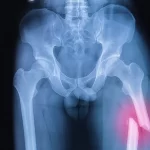

توجه داشته باشید که اشکال شکستگی به چیزی اطلاق می شود که فرد یا پزشک می تواند به صورت بصری ببیند. در حالی که انواع آن با چشم قابل مشاهده نیستند و برای شناسایی نیاز به رادیوگرافی دارند. از انواع شکستگی های مفصل زانو می توان به موارد زیر اشاره کرد:

شکستگی پاتلا باید سریعاً درمان شود. با ایکس ری نوع شکستگی پاتلا تشخیص داده می شود و میزان در رفتگی زانو در اثر شکستن استخوان بررسی می گردد. پزشک با آزمون بلند کردن پا می تواند به میزان آسیب به عضلات چهارسر ران پی ببرد. راه های زیادی برای درمان شکستگی های مختلف زانو وجود دارد، زیرا انتخاب روش مناسب به نوع و شدت آسیب بستگی دارد. به طور کلی، دو رویکرد برای درمان وجود دارد که به شرح زیر است: